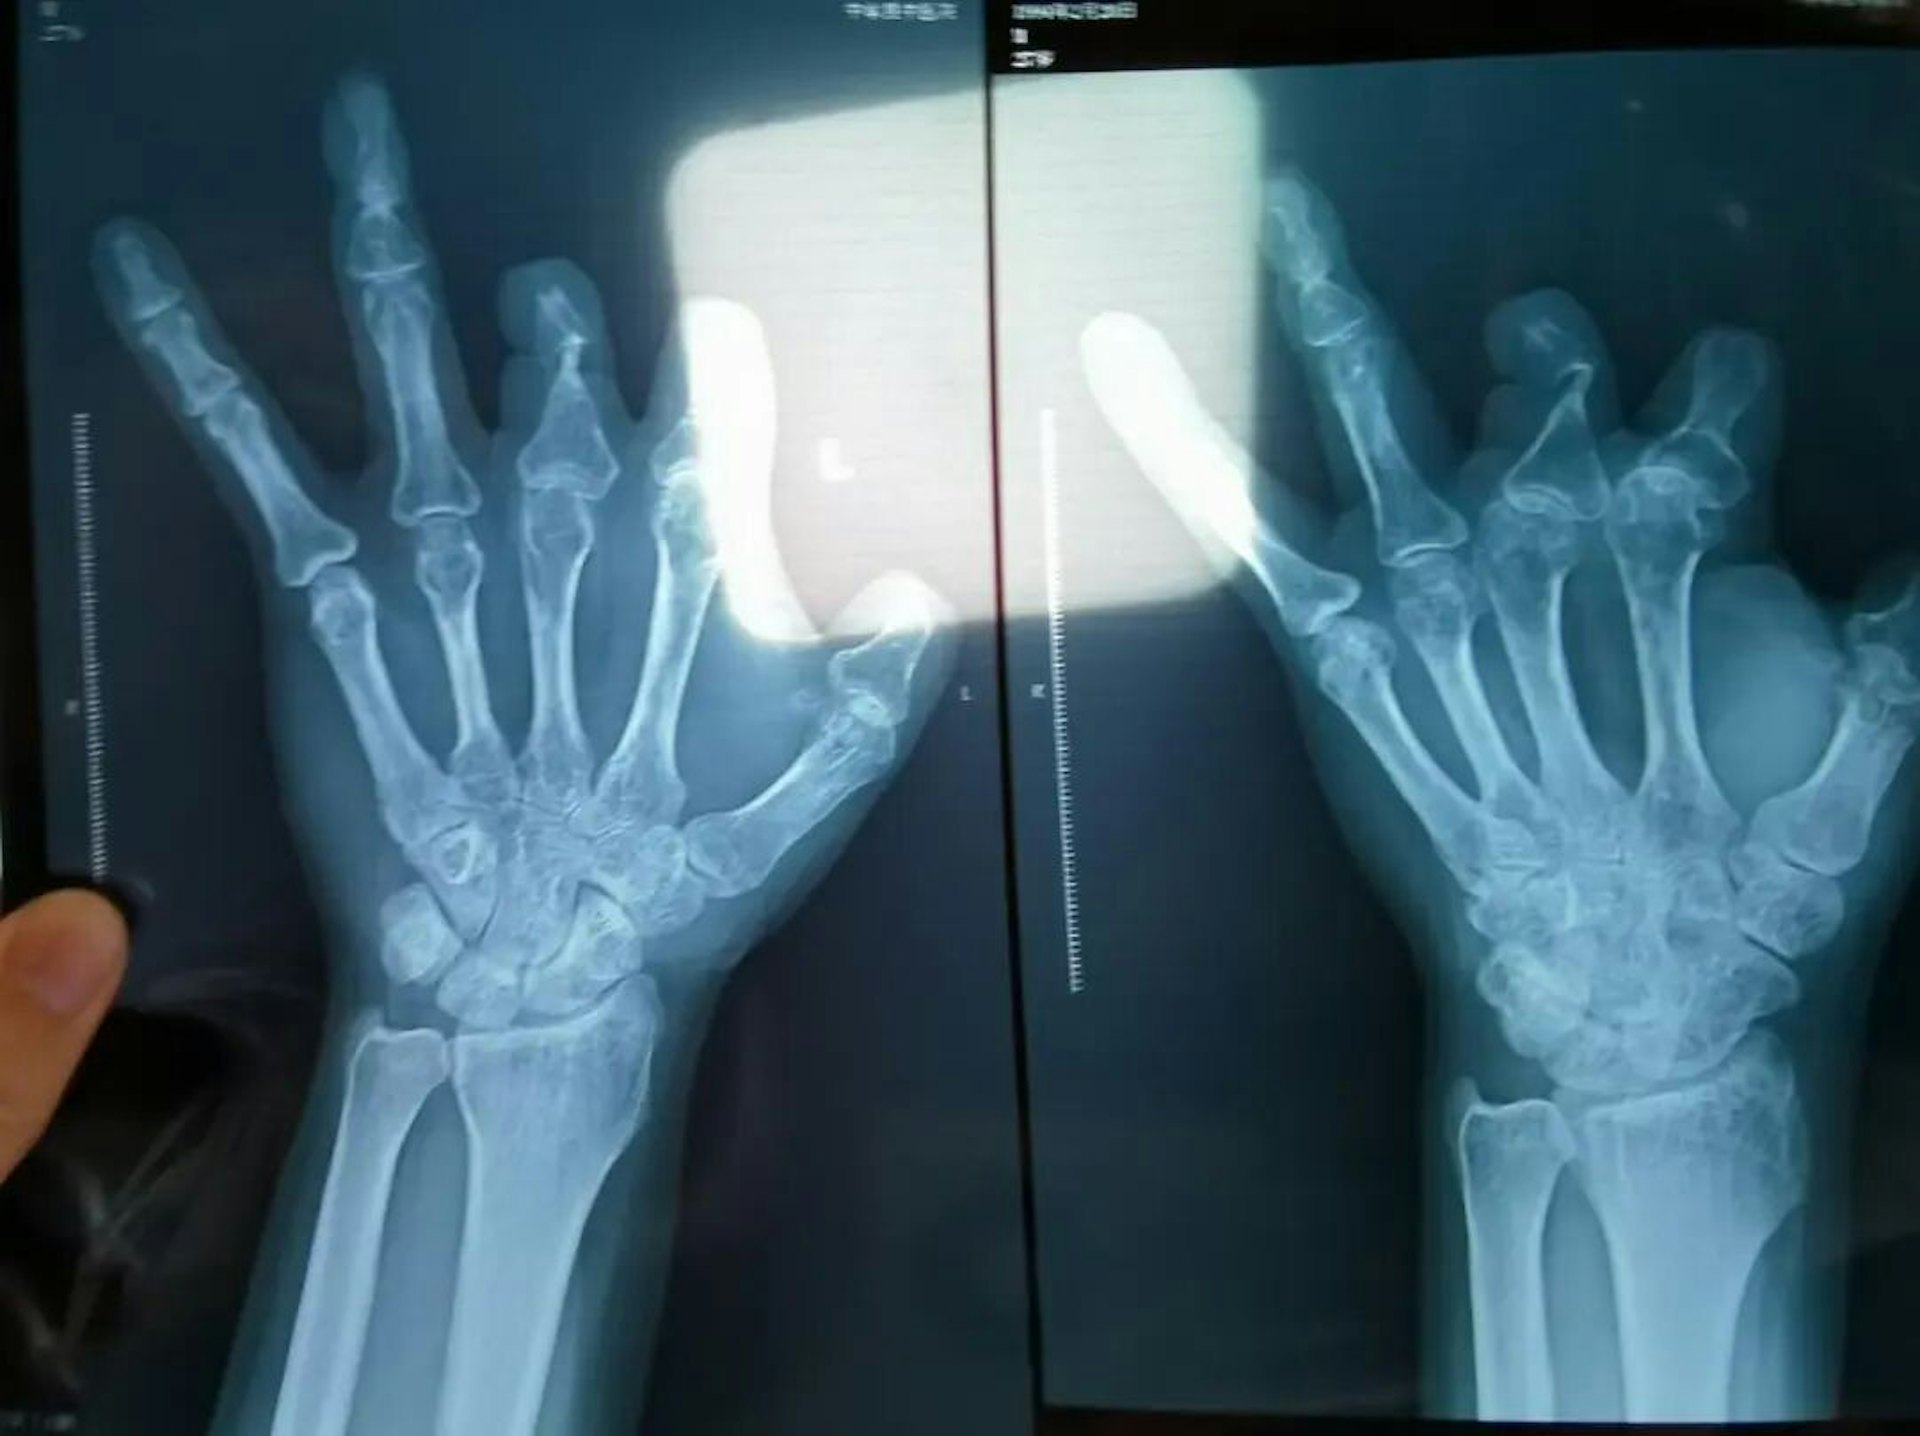

2 s1 j/ o( v. N9 Eos.tvboxnow.com2017年,來自河南的彭先生因意外切傷左手,在鄭州大學第一附屬醫院接受了王福建的手術,術中使用了6個微血管吻合裝置,單價1.68萬元,一共是10.08萬元。但彭先生事後照X光發現這6個微血管吻合裝置在血管內「離奇消失」。

6 v7 B! ?+ ^* B) N$ C公仔箱論壇2021年12月,患者彭先生拍攝的左手X光片,未見收費單據中列出的微血管吻合裝置。(新京報)TVBNOW 含有熱門話題,最新最快電視,軟體,遊戲,電影,動漫及日常生活及興趣交流等資訊。0 d! D& v. v! I

同樣的事件,也發生在王海森身上。2018年,河南一名木工王海森被電鋸切斷了左手拇指。王海森被送入鄭州大學第一附屬醫院做手術,王福建稱為其植入了2個微血管吻合裝置,單價1.68萬元,共計3.36萬元。2021年,王海森照X光後發現,他體內根本沒有這兩個微血管吻合裝置,於是他懷疑「手術時其實沒有使用」並報了案。

患者王海森左手拇指關節以上部位被電鋸切斷,收費單顯示術中使用了微血管吻合裝置,但X光片中未顯示該器械。(新京報)os.tvboxnow.com2 V/ O1 [, w1 M2 R, {